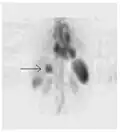

Nuclear medicine tests differ from most other imaging modalities in that nuclear medicine scans primarily show the physiological function of the system being investigated as opposed to traditional anatomical imaging such as CT or MRI. Nuclear medicine imaging studies are generally more organ-, tissue- or disease-specific (e.g.: lungs scan, heart scan, bone scan, brain scan, tumor, infection, Parkinson etc.) than those in conventional radiology imaging, which focus on a particular section of the body (e.g.: chest X-ray, abdomen/pelvis CT scan, head CT scan, etc.). In addition, there are nuclear medicine studies that allow imaging of the whole body based on certain cellular receptors or functions. Examples are whole body PET scans or PET/CT scans, gallium scans, indium white blood cell scans, MIBG and octreotide scans.